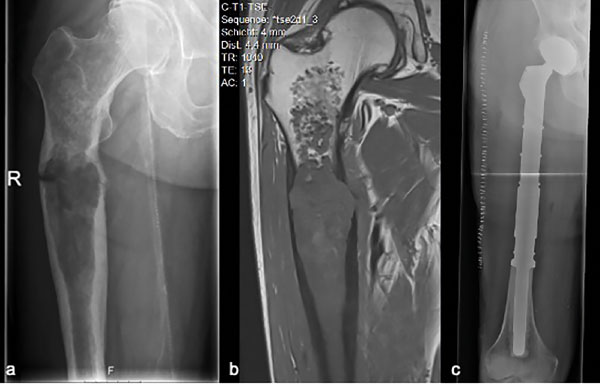

Bei Chondrosarkomen handelt es sich um maligne Tumoren mit hyalin-knorpeliger Differenzierung, bei denen neben der chondroiden Matrix auch myxoide Veränderungen sowie Kalzifikationen oder Verknöcherungen vorliegen können [2]. Neben ihrer morphologischen Heterogenität können Chondrosarkome – wie alle chondrogenen Tumoren – auch hinsichtlich ihrer Klinik und Bildgebung sehr unterschiedliche Erscheinungsbilder zeigen (Abb. 1).

Primäre Chondrosarkome sind dadurch definiert, dass sie sich de novo im Knochen selbst entwickeln, während sekundäre Chondrosarkome auf dem Boden präexistenter (gutartiger) Knochenläsionen wie Enchondromen oder Osteochondromen entstehen (Abb. 1).